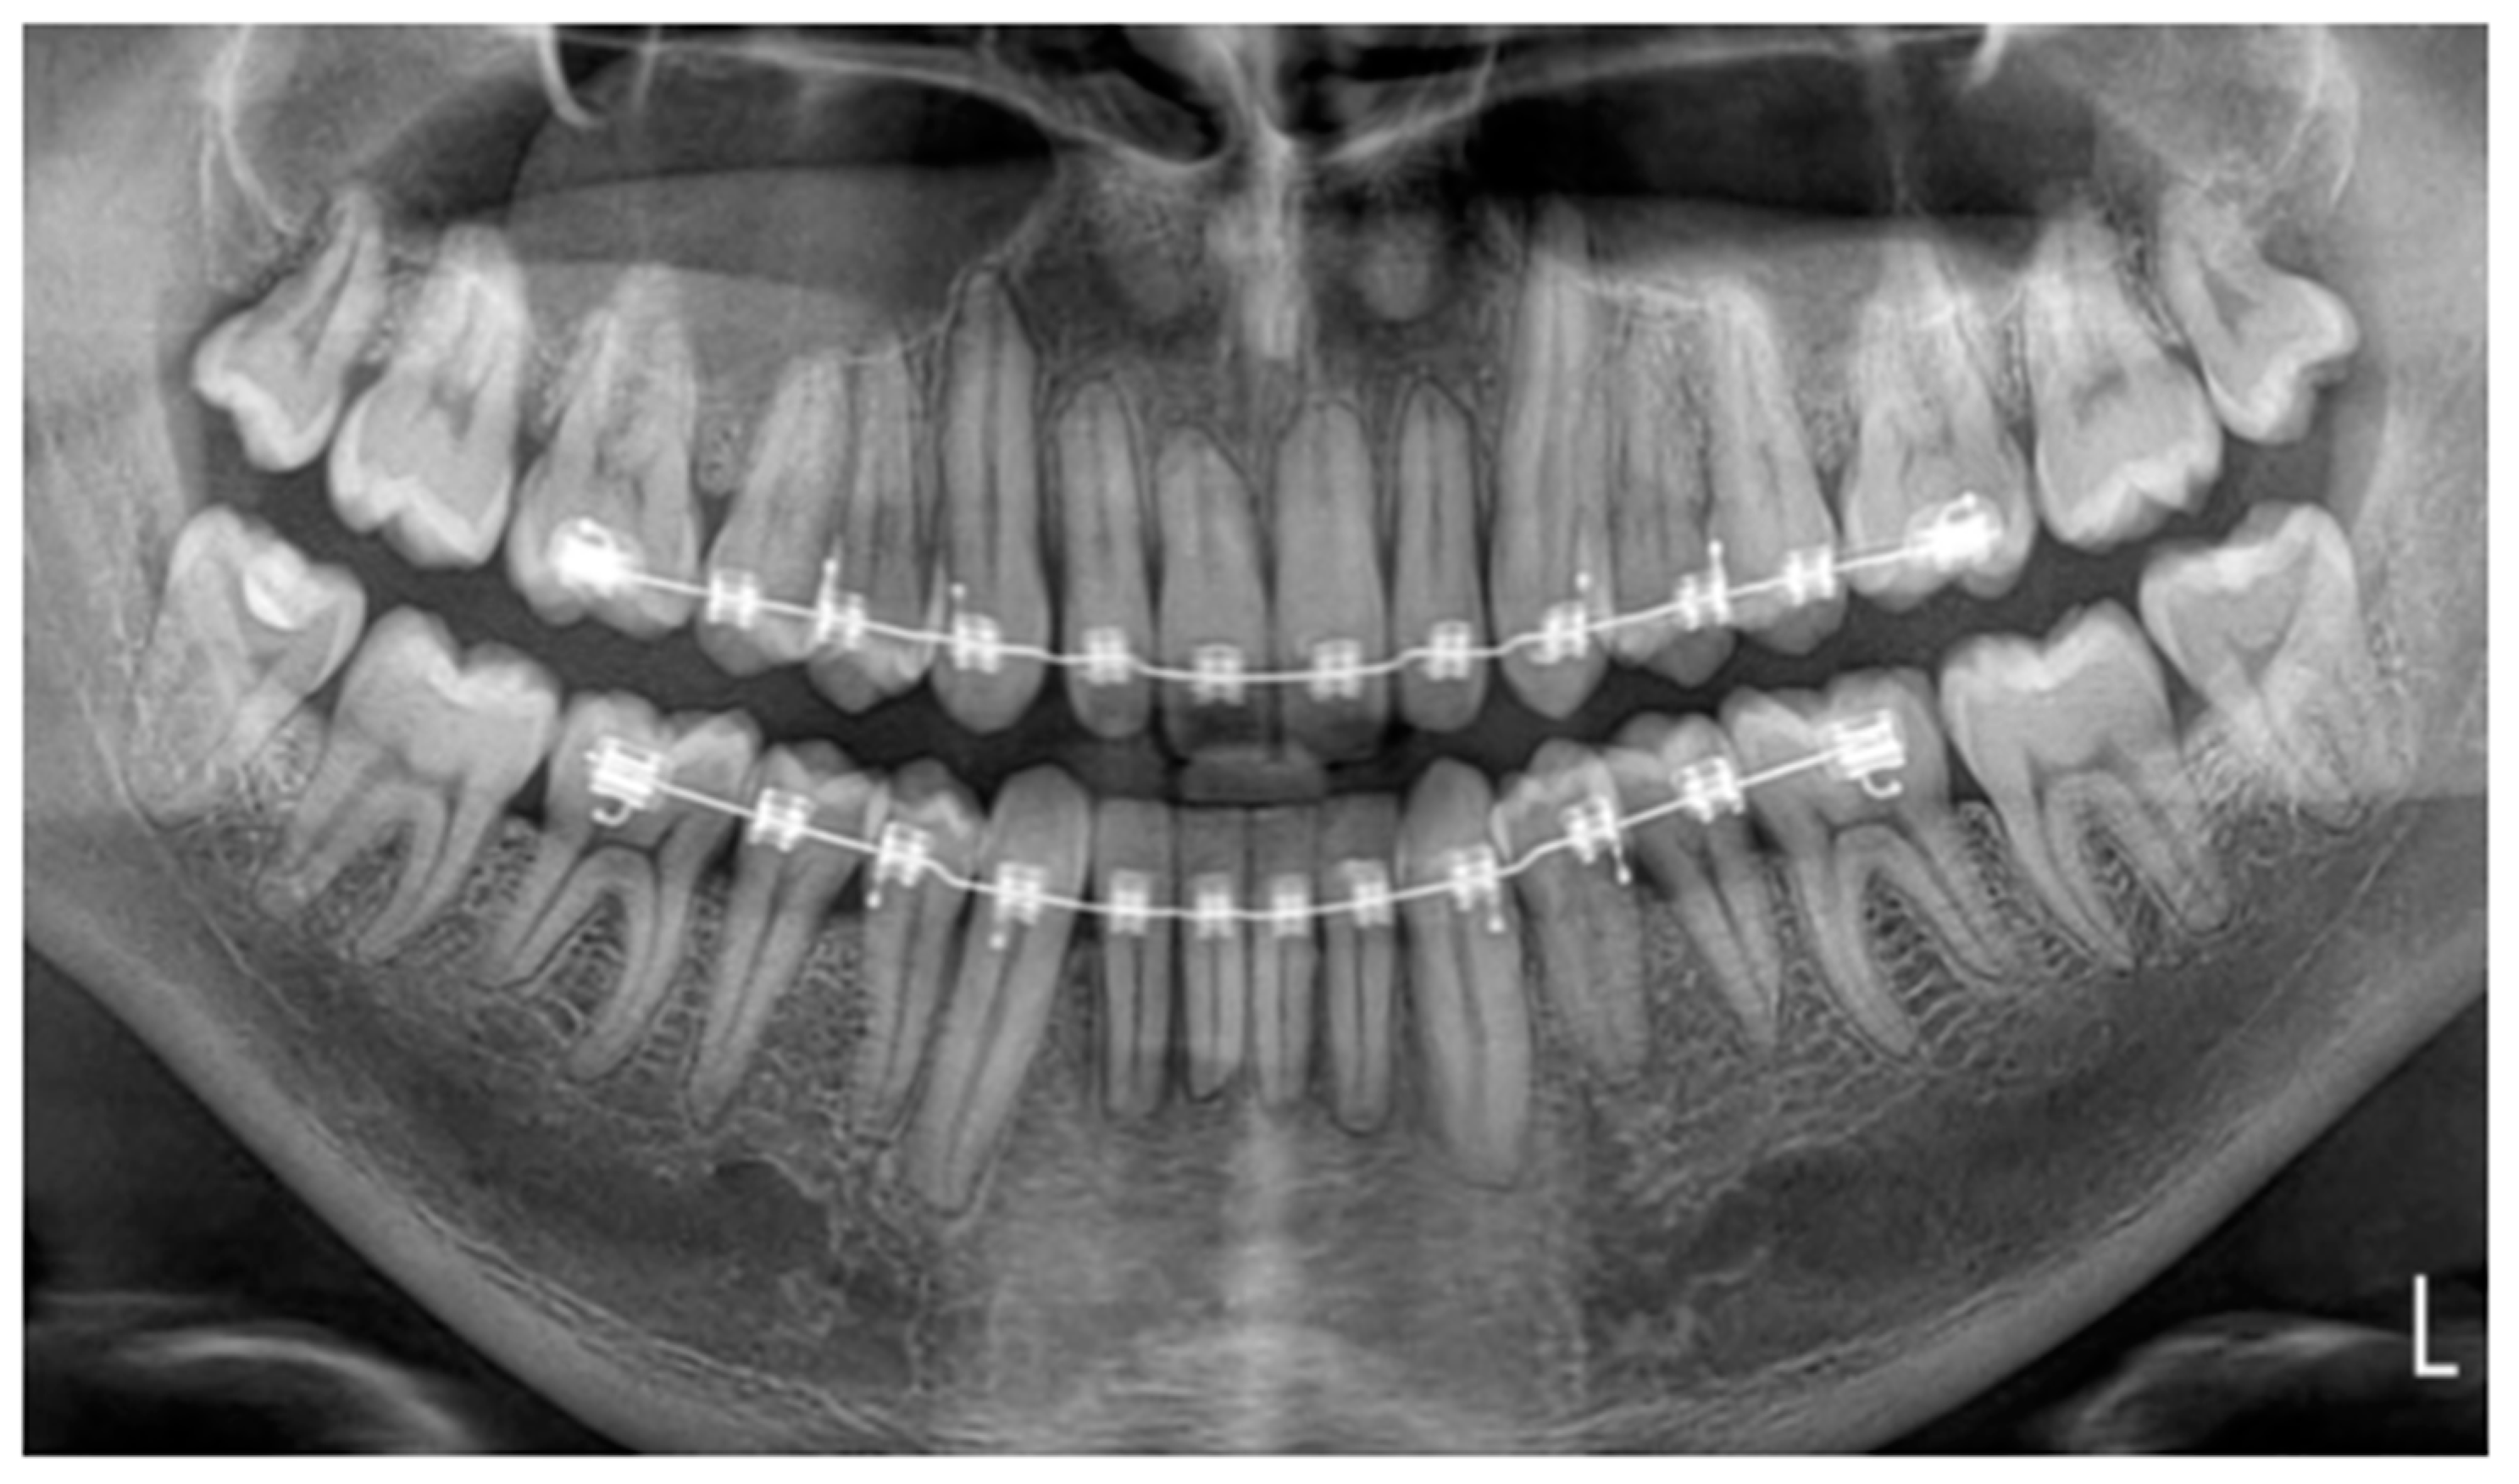

• Therapeutic intervention

To correct the position of the maxillary anterior segment and prevent further misalignment, the patient received orthodontic re-treatment for 2 years and 4 months. The fixed FSWs (0.0195-inch, 3-strand, heat-treated twist wire, Wildcat, GAC International, Bohemia, NY, USA) in the maxilla and mandible were removed. Afterward, fixed appliances were placed (3M Victory Series APC conventional twin brackets, 3M Health Care Division, London, Canada). To correct the excessive palatal root torque of the 13, we incorporated the 13 into the fixed appliances with a 0.012-inch NiTi overlay wire (Sentalloy, Dentsply GAC international, Bohemia, NY, USA) on a 0.016 × 0.022-inch SS base wire (Stainless Steel Ideal® Form, Dentsply GAC international, Bohemia, NY, USA). In this way, the risk of unwanted reactionary tooth movements was reduced. During the active orthodontic treatment, a panoramic radiograph (VistaPano S, Dürr Dental imaging software, Dürr Dental SE, Bietigheim-Bissingen, Germany) was performed to monitor the root resorption observed in the maxillary anterior region in the initial stage of the treatment [24] (Figure 4). It appeared to be stable. However, it was difficult to reach a conclusion in this regard, since (1) a great difference in the tooth position between the two panoramic radiographs and (2) variations in quality between the panoramic radiographs were observed due to the use of different radiographic devices. The oral hygiene was checked at every orthodontic appointment. If necessary, instructions were given to maintain the quality of the patient’s oral hygiene during the orthodontic treatment. After active orthodontic treatment over 2 years and 4 months, the treatment result was stabilized with fixed braided-rectangular-wire (BRW) retainers (Forestaflex, Forestadent®, Bernhard Förster GmbH, Pforzheim, Germany) located at 12–22 and 33–43. We opted for the BRW retainers, which achieve better torque control compared to flexible spiral wires (FSW) [25]. In addition, a VFR was prescribed for approximately 10 h a day to cover all the maxillary teeth. According to the current literature, the part-time wear of the VFR should be sufficient enough to generate stability [26]. Table 1 provides a detailed overview of the interventions.

Figure 4. Panoramic radiograph during orthodontic treatment for monitoring root resorption.